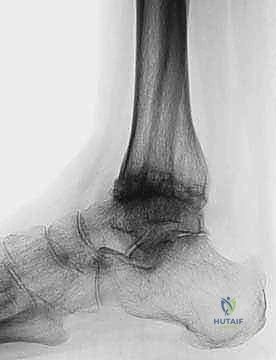

FIG 6 • The TNK ankle replacement for rheumatoid arthritis of the ankle (cemented replacement). A. Preoperative AP view. B. Preoperative lateral view. C. Postoperative AP view 2 years 6 months after the surgery. D. Postoperative lateral view.